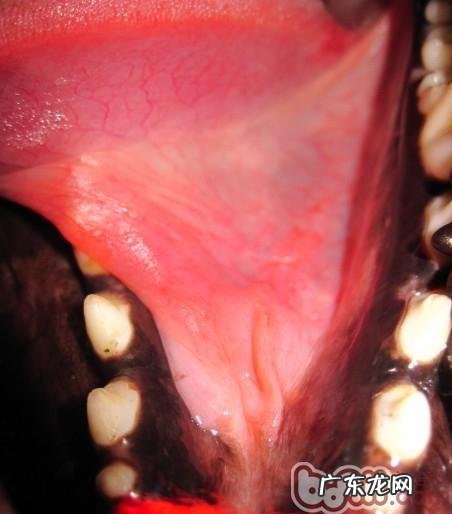

文章插图

图5 右边舌下囊肿(病案二)